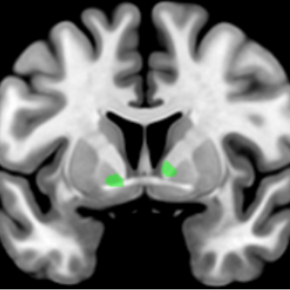

© Andry Andrianarivelo et Peter Vanhoutte - Laboratoire Neuroscience Paris-Seine (CNRS/Sorbonne Université/Inserm)